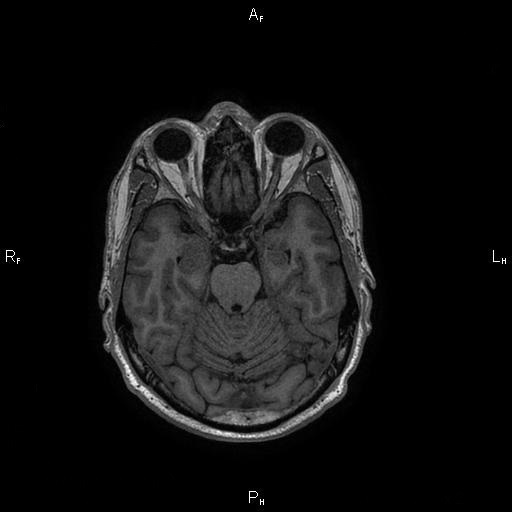

6. Рис. 2а

Тема

Тип Материалы исследования

Посмотреть (28KB)

Метаданные ▾

7. Рис. 2б

Посмотреть (33KB)